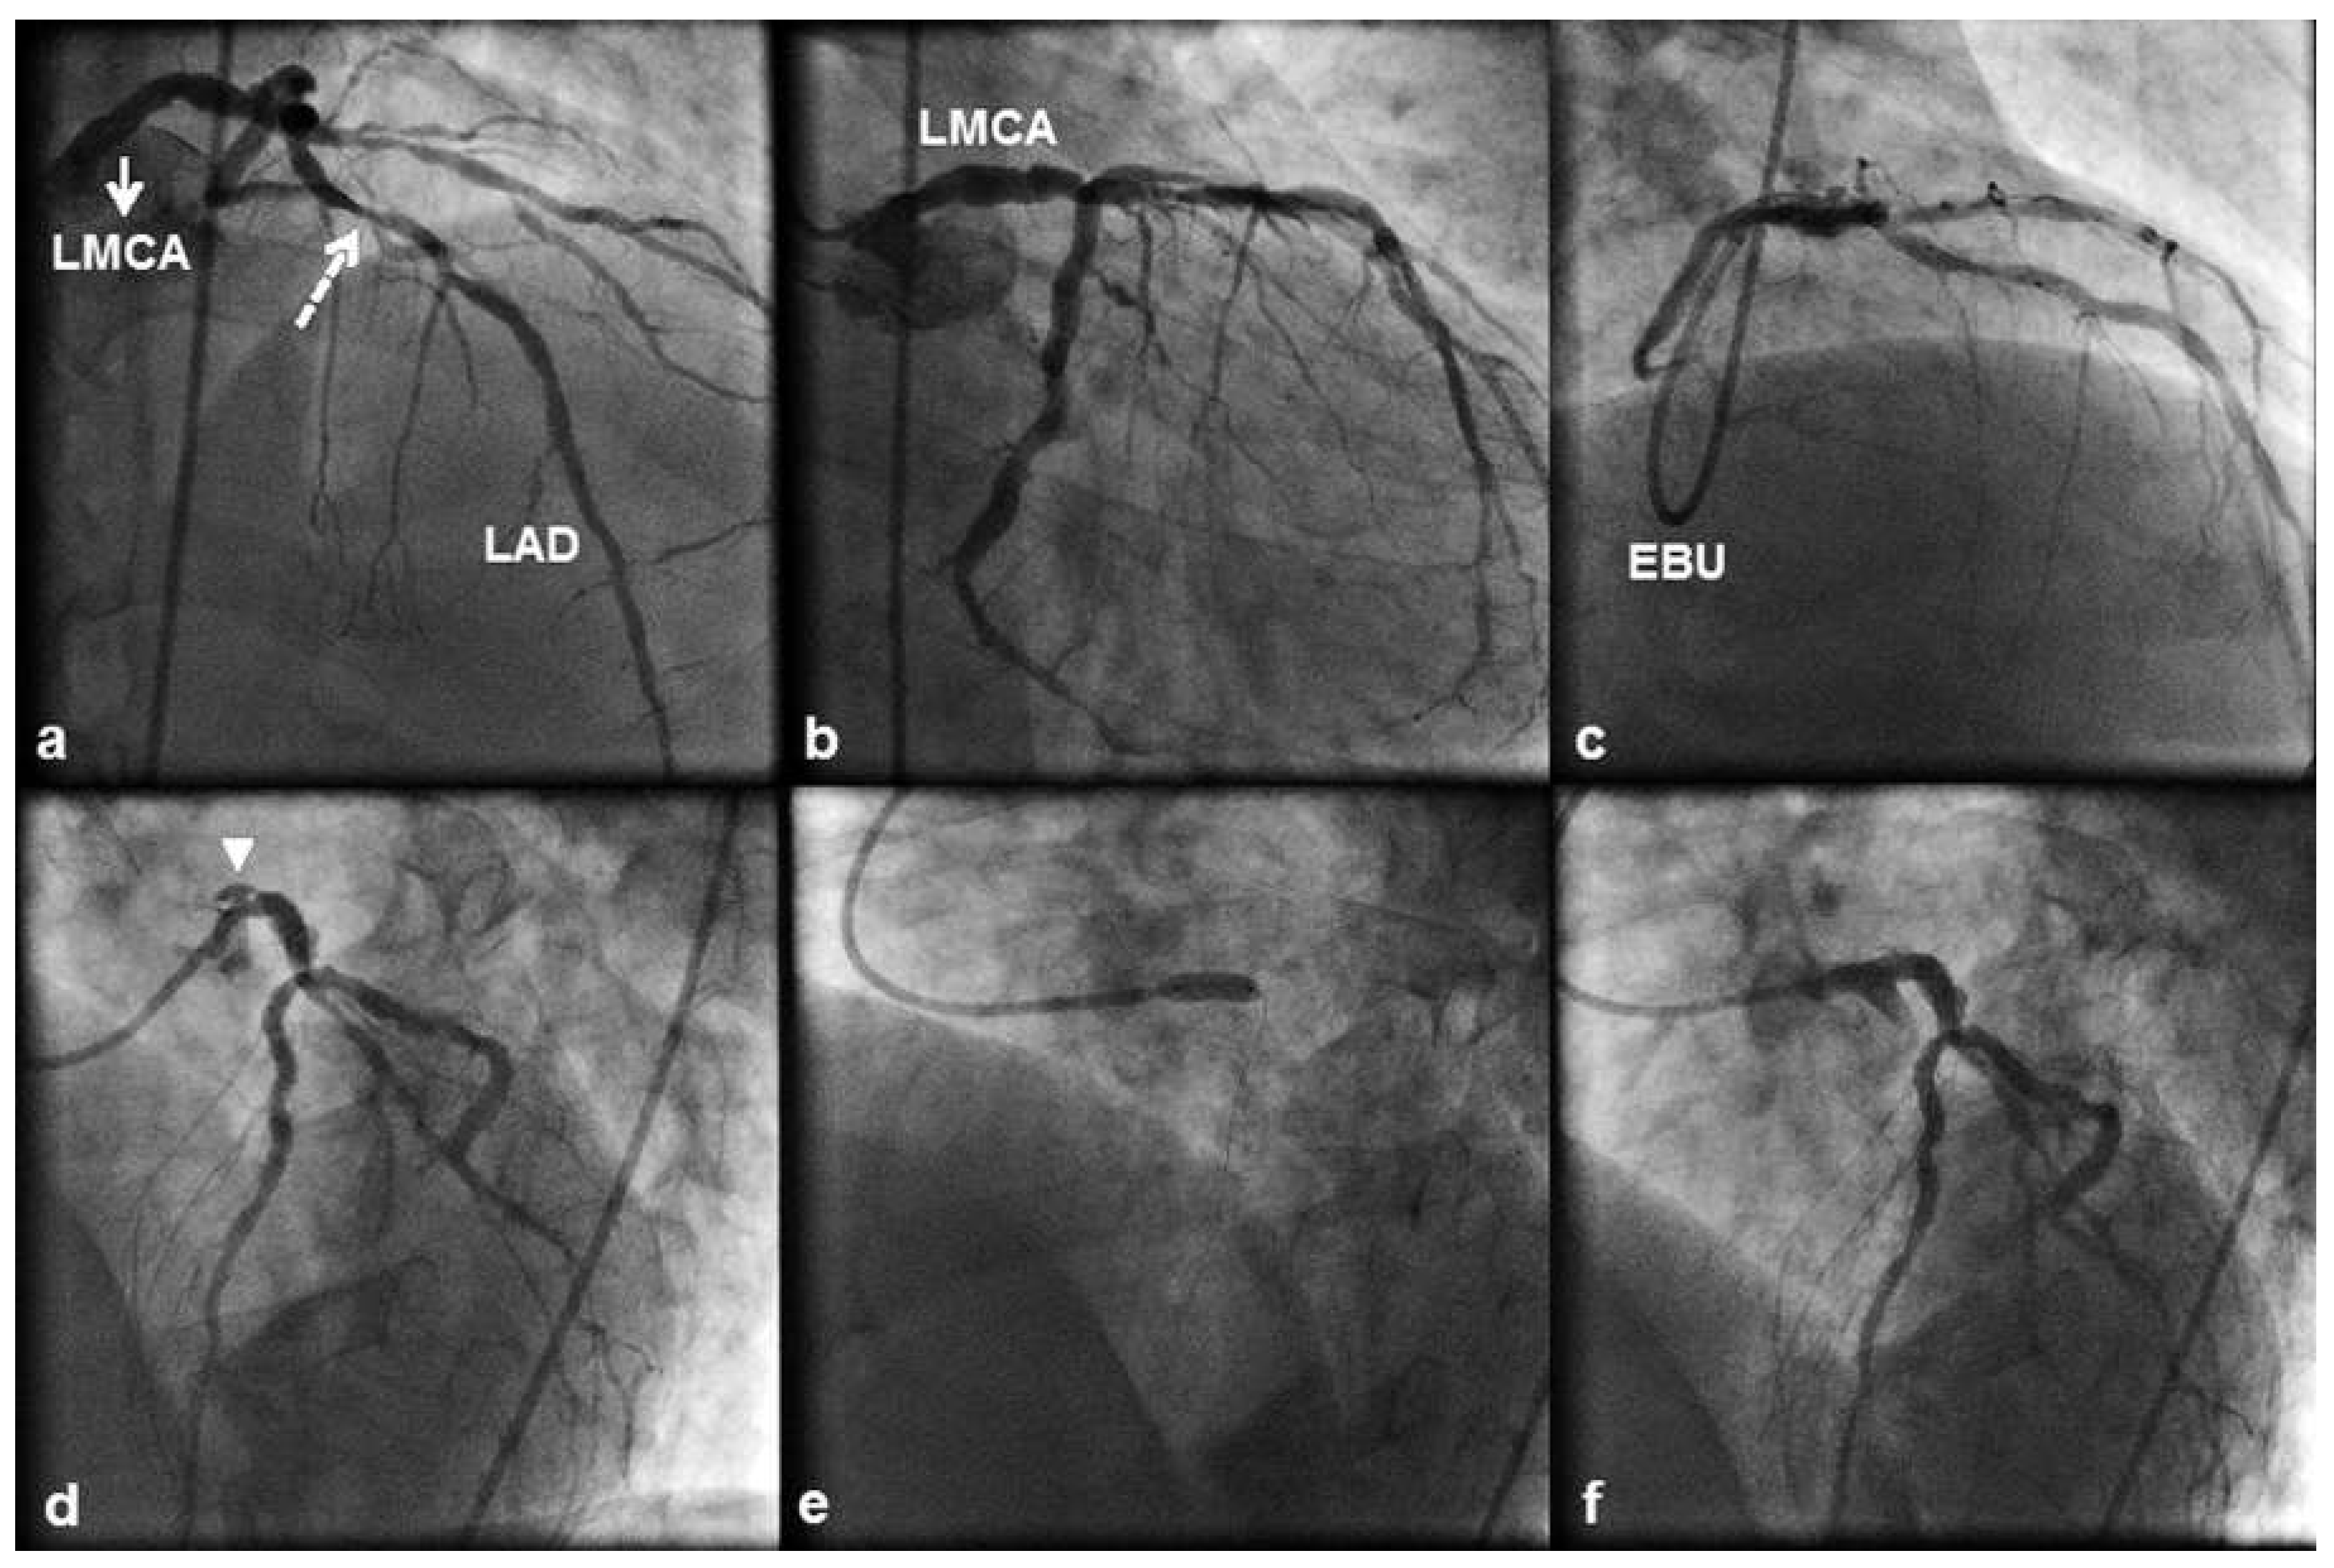

A 58 year old male patient with a history of hyperlipidaemia and cigarette smoking underwent transfemoral coronary angiography because of stable angina and ischaemia over the LAD artery territory, demonstrated with dobutamine stress echocardiography. Angiography showed diffuse nonobstructive LMCA disease (Figure 2a, b), significant proximal LAD disease (Figure 2a) and chronic occlusion of a left posterior descending artery with faint filling through bridging collaterals. Therefore, we proceeded with PCI to the LAD artery lesion. The LMCA was engaged with a 6 French EBU 4.0 guiding catheter, and a 3.5 × 13 mm DES was directly implanted across the lesion (Figure 2c). Shortly thereafter the patient complained of acute, severe chest pain, and after multiple views focal and persistent extraluminal contrast staining that was compatible with a type C ostial LMCA dissection (Figure 2d) was revealed. The dissection was directly stented with a 4.0 × 15 mm DES (Figure 2e). Stent postdilation was performed with a 4.5 × 15 mm noncompliant balloon with a good final angiographic result (Figure 2f). Postprocedural creatine kinase and creatine kinase MB isoenzyme levels were normal, and the patient was discharged home after a 2 day uneventful hospital course. He was prescribed life long dual antiplatelet therapy. He remained stable 3.0 years after stenting with Canadian angina class I and no evidence of a cardiovascular event.

Figure 2. (a) 10° right anterior oblique (RAO) 40° cranial view of the left coronary artery displaying significant proximal left ante- rior descending (LAD) artery disease (dashed arrow). The left main coronary artery (LMCA) (a,b) contained substantial ather- oma but no significant stenosis. (c) 40° RAO 40° cranial view obtained through a 6 French Extra Back-up (EBU) 4 guiding catheter showing the LAD artery stent deployment position. (d) 40° left anterior oblique (LAO) 20° cranial view after stenting displaying contrast outside the coronary lumen (“extraluminal cap”) at the LMCA ostium (arrowhead), which persisted after contrast had cleared from the coronary lumen (type C coronary dissection). (e) Stent deployment across the dissection. (f) 40° LAO 20° cranial view showing an optimal angiographic result with complete sealing of the dissection flap.

The RCA is the most frequently dissected vessel (84– 87% of the cases), followed by the LAD, left main coronary and LCx arteries [16,17]. Iatrogenic dissection of both the RCA and LMCA is mostly observed after inadequate alignment of a diagnostic or guiding catheter (1,2,4), yet the LMCA and RCA arise from their respective aortic sinuses at different angles: acute (range 20°– 55°) and almost perpendicular (range 60°–88°), respectively. This might render the LMCA less susceptible to catheter induced dissection by providing a better approach for catheterisation [17]. Three retrospective case series have reported the incidence of iatrogenic LMCA dissection during a coronary catheterisation procedure (PCI or diagnostic coronary angiography). Lee et al. [1] reported an incidence of 0.03% (10 cases out of 34 190 procedures), Cheng et al. [2] an incidence of 0.071% (13 cases out of 18 400 procedures), and Eshtehardi et al. [4] an incidence of 0.07% (38 cases out of 51 452 procedures) with a twofold greater incidence of iatrogenic LMCA dissection during PCI (0.1% of all PCIs) than during diagnostic coronary angiography (0.06% of all diagnostic coronary angiographies). Dissection of the LMCA is most frequently caused by inappropriate positioning of the diagnostic or guiding catheter, with an incidence of 61.5% in the study by Cheng et al. [2] where a 6 French catheter was used in 84.6% of the cases, the Kimny miniradial catheter in 61.5% of the cases and the left Judkins catheter in 30.8% of the cases. Balloon dilation near the LMCA bifurcation and stenting at the LAD artery ostium were the second and third most frequent causes of LMCA dissection in this study, with an incidences of 23.1% and 7.7%, respectively. In the study by Eshtehardi et al. [4], inappropriate positioning of a diagnostic catheter was implicated in 58% of the cases of LMCA dissection where the left Judkins catheter was used in 82% of the cases; inappropriate positioning of a guiding catheter was implicated in 16% of the cases of LMCA dissection where extra backup catheters (Amplatz left , EBU- or Q curve) were used in 56% of the cases. The second most frequent cause of LMCA dissection in this study was deep intubation of the guiding catheter during balloon retrieval, which was observed in 26% of the cases. In our first case, as shown in Figure 1b, the 6 French EBU 4.0 guiding catheter was non coaxially positioned and its tip abutted against the wall of the LMCA ostium without, however, causing pressure damping or ventricularisation. However, such a catheter position suggested that the catheter might have been “too short” for the patient and that a more coaxial LMCA engagement could have been achieved with an EBU 4.5 guiding catheter. Dissection of the LMCA occurred secondary to deep seeding of the guiding catheter and scraping of the LMCA wall during retrieval of the postdilating balloon. If we had disengaged the guiding catheter from the LMCA and pulling, to keep the catheter out of the LMCA ostium, had been more vigorous to withstand the resistance met during retrieval of the postdilating balloon, we would have prevented deep seeding of the guiding catheter and the resultant LMCA dissection. In our second case, the LMCA contained substantial, but nonobstructive atheroma. As shown in Figure 1d, the 6 French EBU 4.0 guiding catheter was non coaxially positioned with its tip pointing vertically against the roof of the LMCA. Accordingly, a hydraulic LMCA dissection might have been created during contrast injection. Keeping the catheter coaxially positioned during every minute of the procedure, avoiding contrast media injection in the presence of pressure damping or ventricularisation and gradual ramping of the injection are essential actions in order to minimise the risk of LMCA dissection.